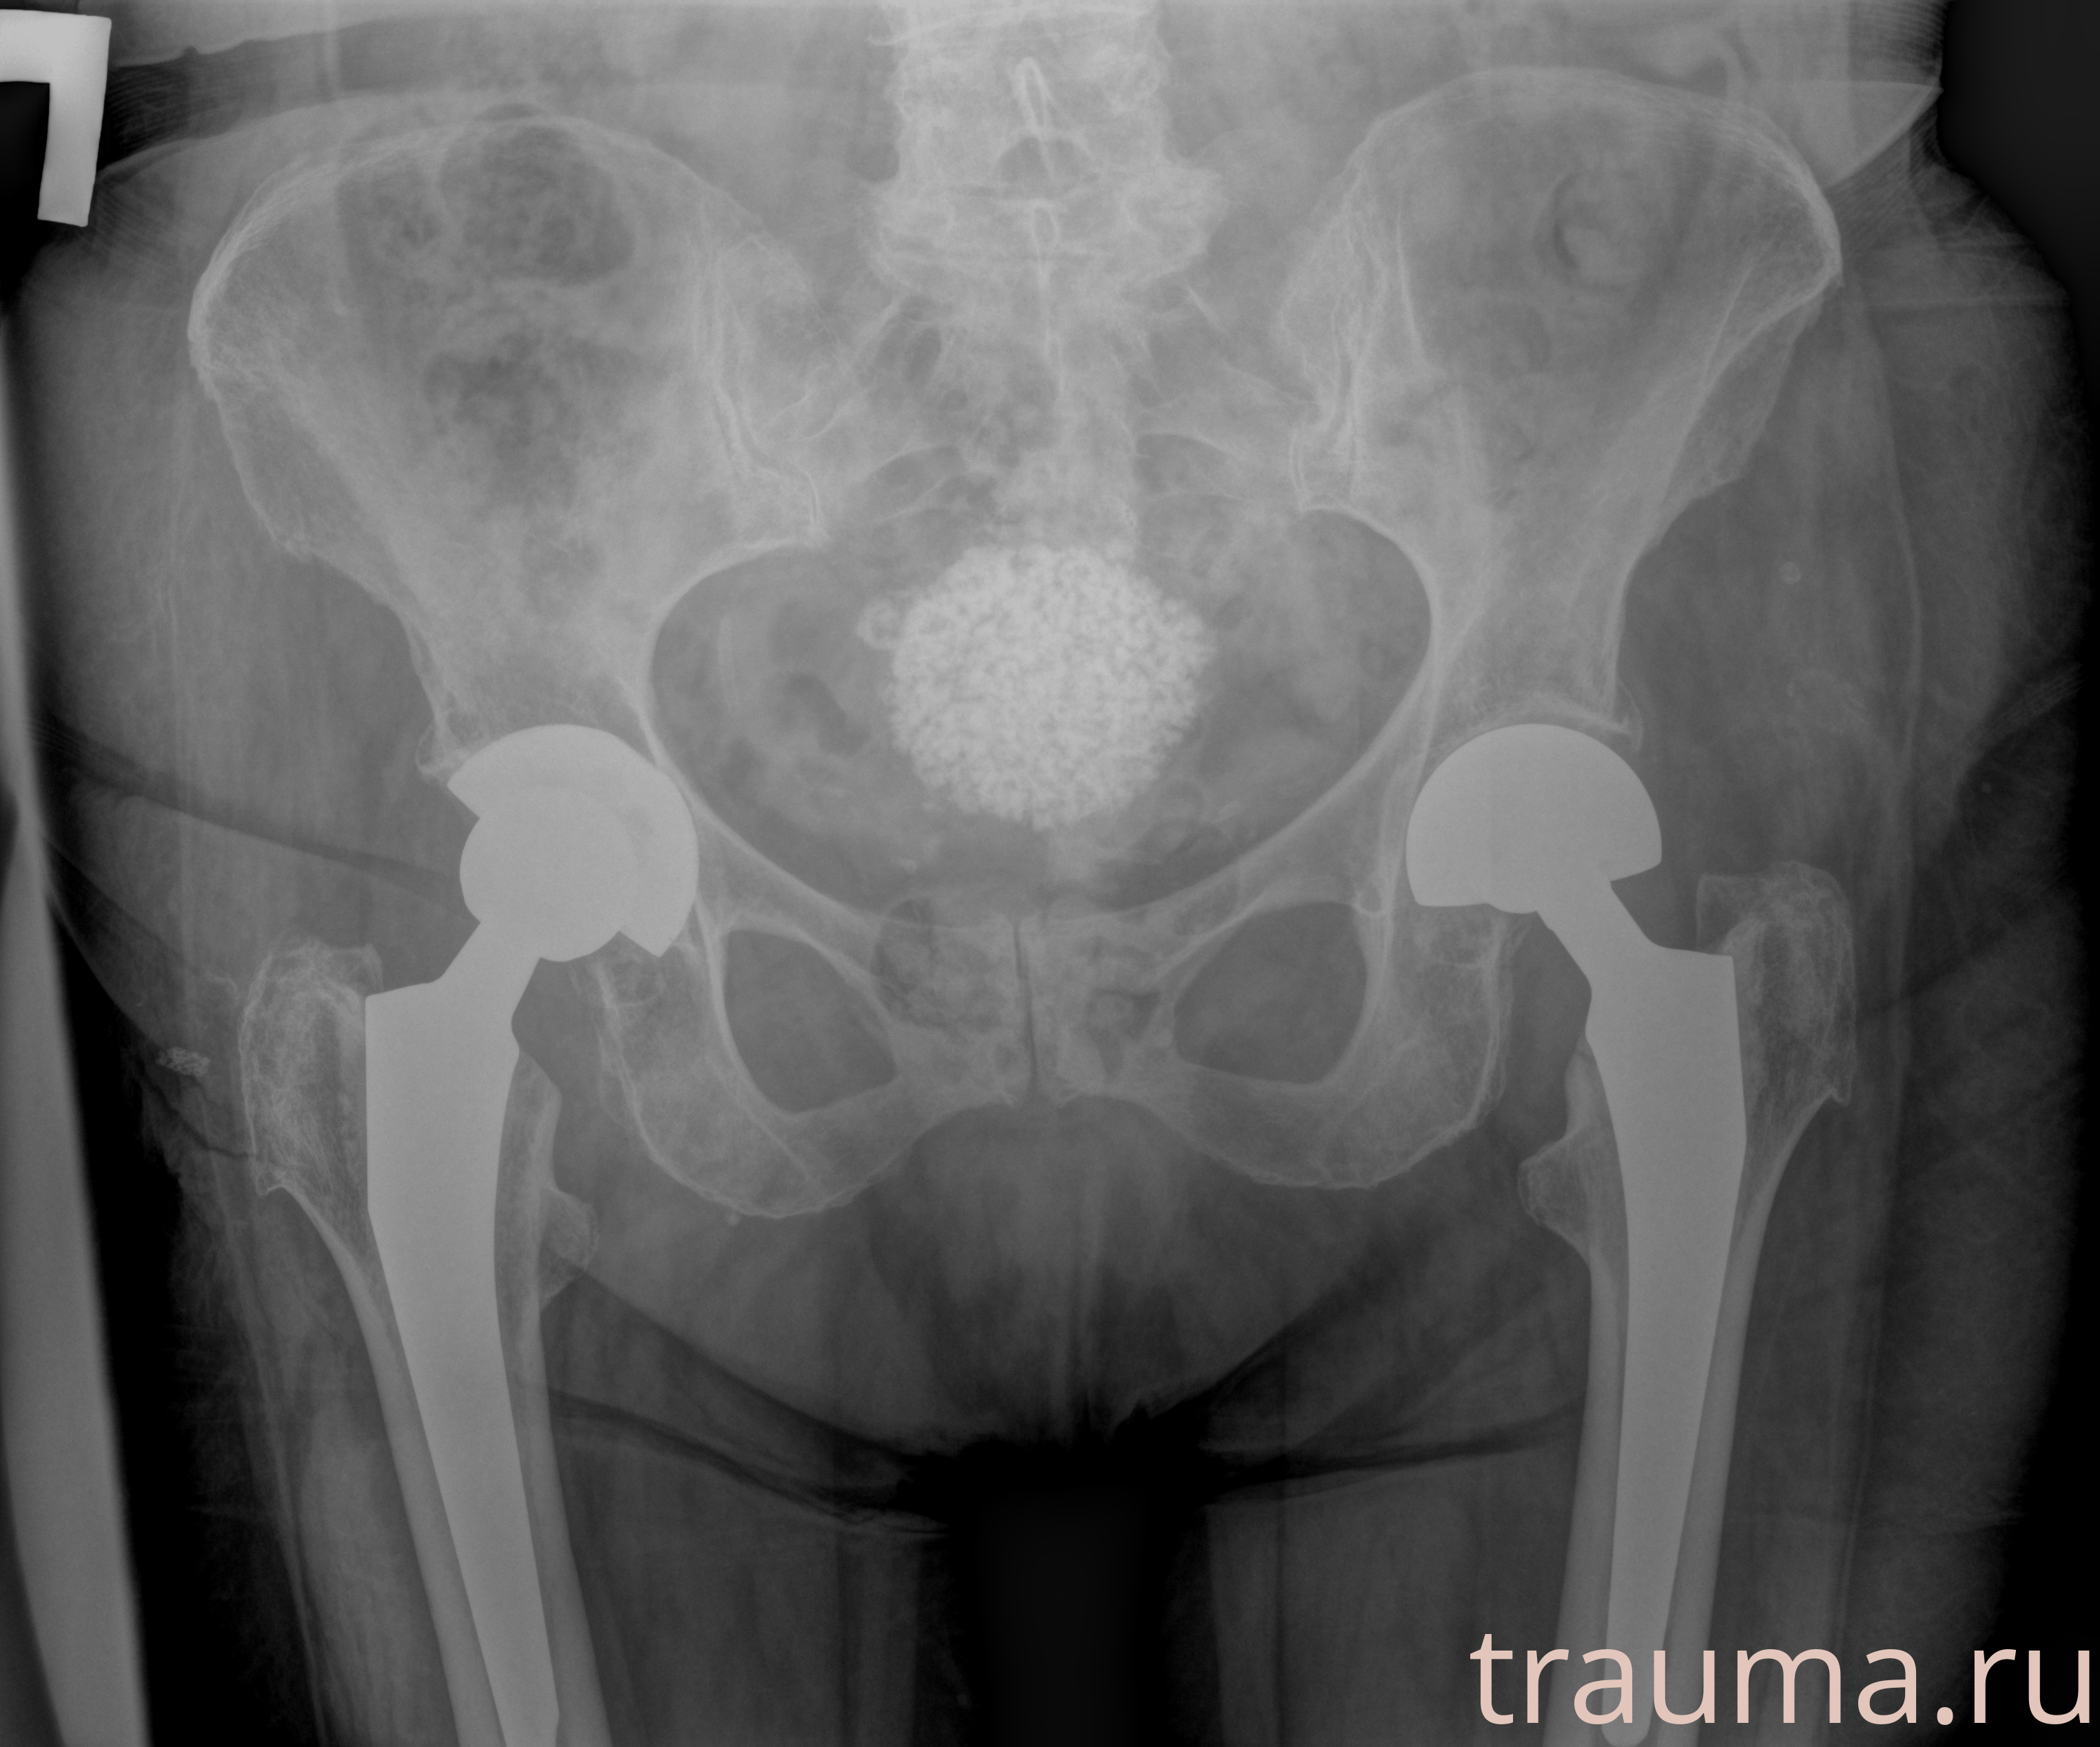

Рентген на дому: по вашему адресу приезжает врач-рентгенолог, травматолог-ортопед с мобильным рентгеновским аппаратом, проводит диагностику травмы или заболевания, делает необходимые рентгенограммы, дает рекомендации по дальнейшему лечению. Получить качественные снимки в домашних условиях возможно благодаря уникальной методике, разработанной МосРентген Центром для института  Склифосовского